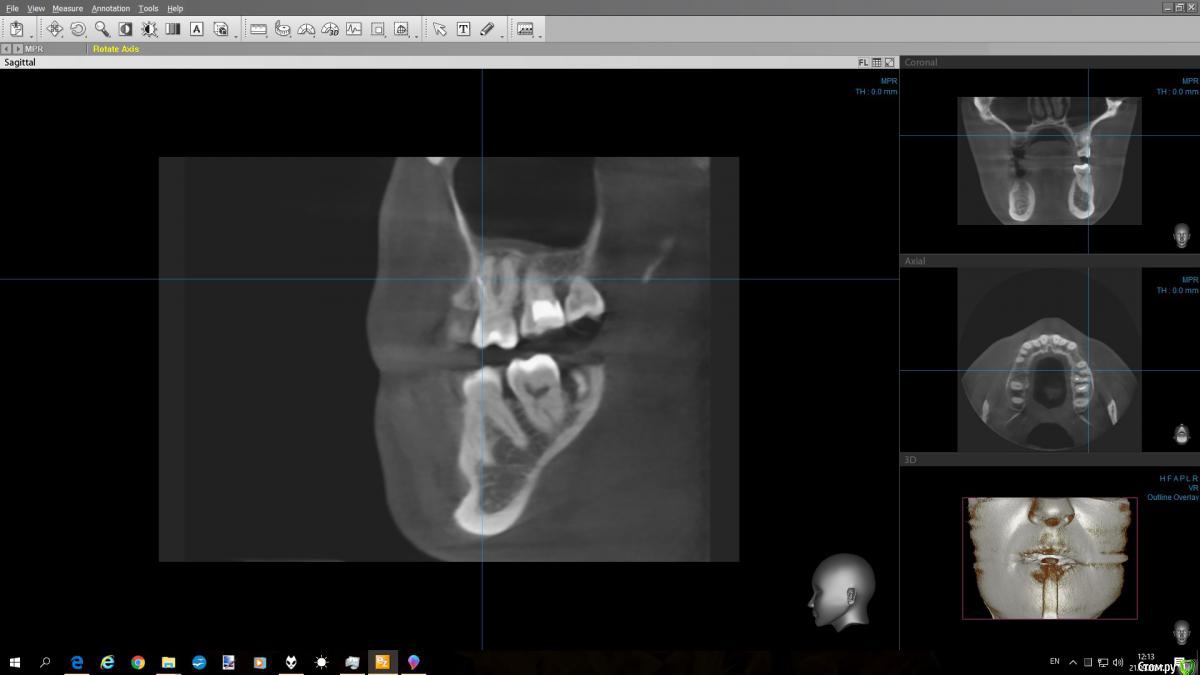

С кастрюлькой Опубликовано 21 сентября, 2017 Автор Поделиться Опубликовано 21 сентября, 2017 (изменено) Добрый день! Во вложении снимок этого зуба, как смогла выделила.. Можно ли будет дать ответ ? Изменено 21 сентября, 2017 пользователем С кастрюлькой Ссылка на комментарий

wladdX Опубликовано 21 сентября, 2017 Поделиться Опубликовано 21 сентября, 2017 (изменено) скриншоты Изменено 21 сентября, 2017 пользователем wladdX Ссылка на комментарий

DmitrySH Опубликовано 21 сентября, 2017 Поделиться Опубликовано 21 сентября, 2017 Удаляйте Ссылка на комментарий

red_butler Опубликовано 22 сентября, 2017 Поделиться Опубликовано 22 сентября, 2017 + 1 удалять Ссылка на комментарий